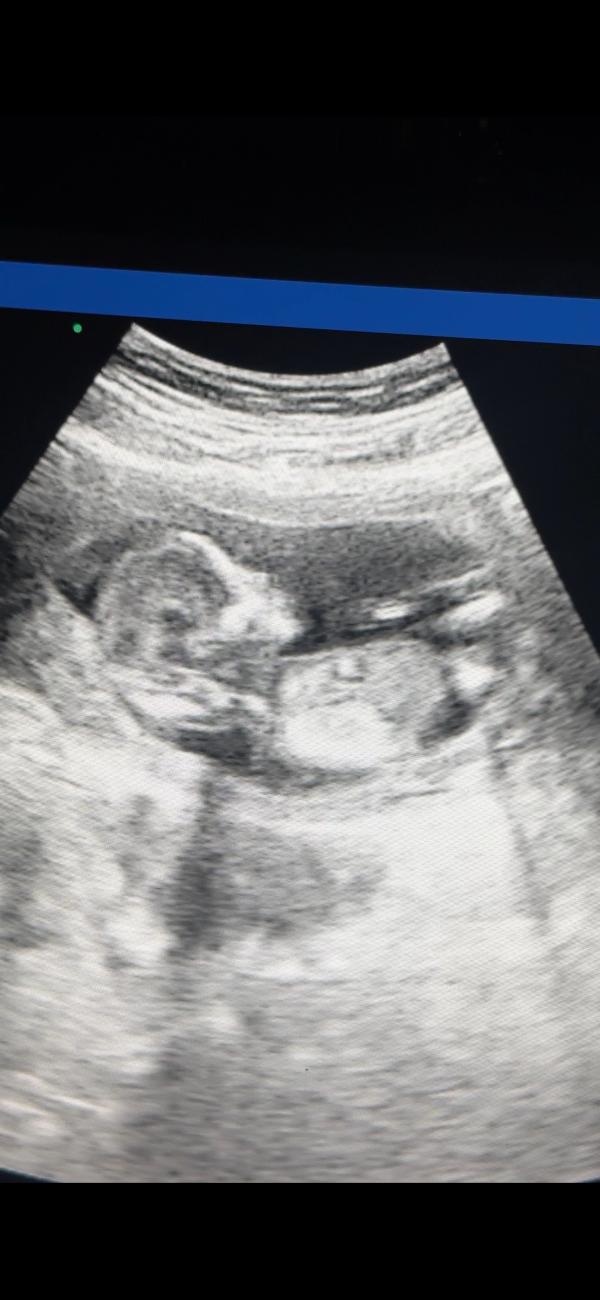

Навязчивое желание проверять сердцебиение на УЗИ

Рубрика: навязчивое желание на каждом дежурстве проверять сердечко 😅 *когда ты сильно отрицаешь доплеры с вб*

Человек потребовал покушать ночью и на узи икал видимо, как я его понимаю 🤭